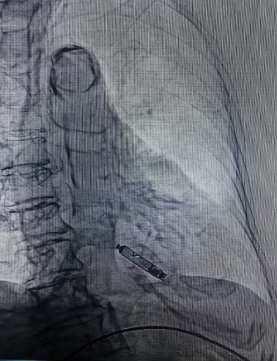

术后起搏器影像

术后程控参数良好,电池预估能用19.9年